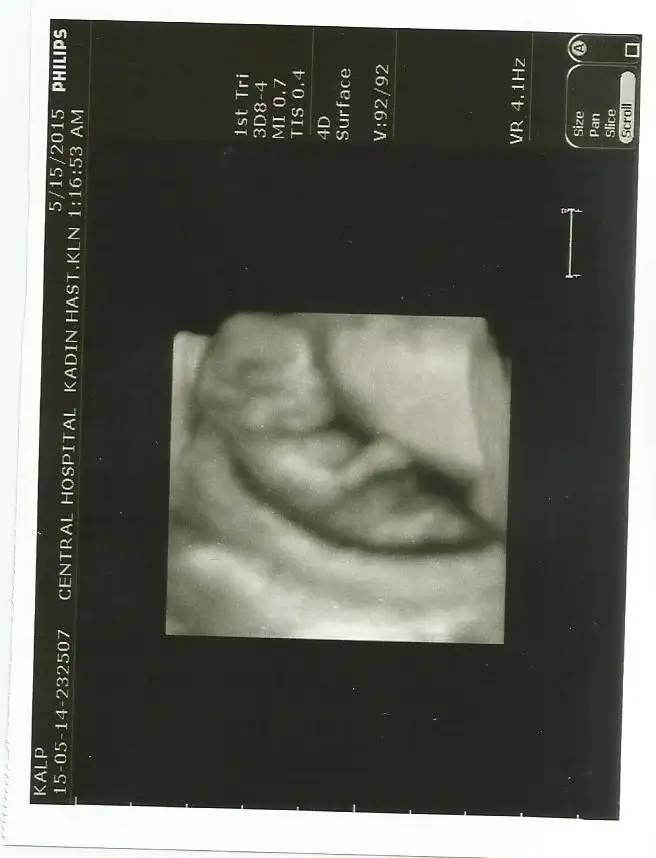

Canım doktorun erkek dediği resmi de koyar mısın?Bebeğimin cinsiyeti belli oldu ERKEK